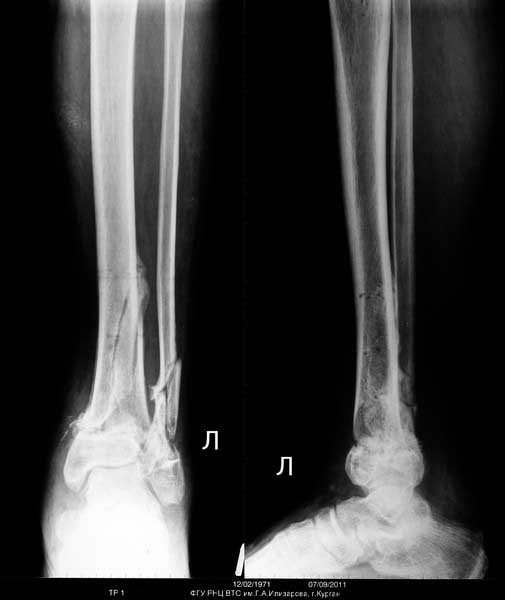

Желательно указать активность пациента до травмы и возраст. Из снимков не хватает бокового снимка бедра и полного на всю длину снимка голени.

С момента травмы прошло более трех месяцев, и тактика лечения по восстановлению функциональной конечности отличается от первичного остеосинтеза. Не надо гоняться за идеальным сопоставлением костных отломков, а надо вести работу по восстановлению опороспособности конечности.

Большая деформация бедренной кости, и поэтому желательно первоначально восстановить бедро. Остеоклазия бедра - это контролируемое мероприятие, и в большинстве не нуждается в донорской крови. Предварительный наружный фиксатор с дистракцией поможет создать запас, что облегчит окончательный остеосинтез без усилий. Закрытый остеосинтез -привлекательный вариант, хотя не исключается подправить что то во время операции через малый доступ.

Для оценки степени сращения костей голени рекомендуется сделать КТ срезы. И возможно, для голени не надо предпринимать ничего. Там процесс консолидации заканчивается, и хотя форма далека от идеала, но не так уж плоха. Уже время для нагрузки, и дайте возможности нагружать! Время покажет, и в зависимости от активности в дальнейшем можно обсудить план лечения в будущих дисскуссиях.